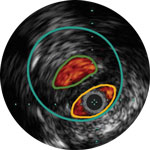

Behandlungsplan Beispiel 2

Lumen mit frischem Thrombus

Mikrokalzifizierung

Kalzifizierte Plaque mit Schallschatten

Gefässgrösse: 6 mm Durchmesser Plaquemorphologie: gemischte, thrombotische Plaque mit mittlerem Calcium Plaquegeometrie: exzentrische Läsion Position des Führungsdrahtes: wahres Lumen

Quick-Cross-Katheter: souverän komplexe Morphologien durchqueren Turbo-Power-Laser-Atherektomie: vorwärts gerichtetes, direktionales Abtragen zur Beseitigung von Thromben; Rotation für verbessertes Abtragen in kalzifizierten Läsionen AngioSculpt Scoring-Ballonkatheter: sicheres Aufweiten von Reststenosen4 Stellarex DCB: entwickelt für hohe Leistungsfähigkeit bei Kalfizifierungen